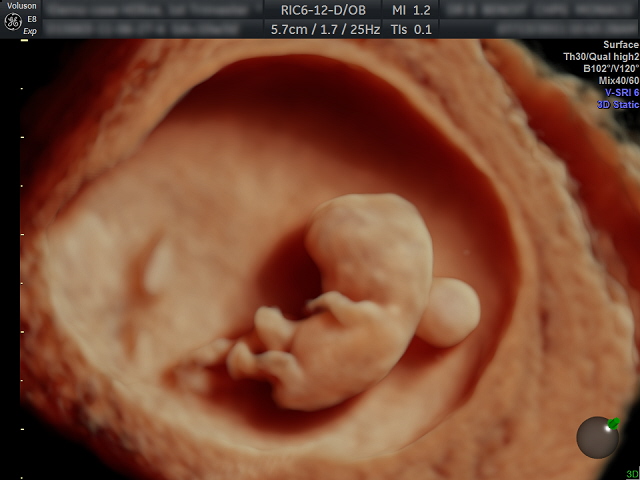

Ecografía. La ecografía es el método de exploración imprescindible en el ámbito del diagnóstico prenatal. Tiene unos momentos clave de aplicación:

En el primer trimestre. Nos permite detectar algunas imágenes consideradas "marcadores de cromosomopatías". La más válida y aceptada en los últimos años es la conocida como “translucencia nucal”, estructura visualizable en el dorso del feto entre la semana 11 y 14. Si supera ciertas dimensiones (3 mm.), deberíamos ofrecer la realización de prueba invasiva. Igualmente importante es visualizar el hueso nasal, pues su ausencia se ha relacionado con el Síndrome de Down.

En el segundo trimestre. Especialmente alrededor de la semana 20, es la época más adecuada para el diagnóstico de la mayoría de malformaciones de tipo anatómico. Debe practicarse por personal especialmente cualificado, preparado y acreditado para este tipo de ecografías. Igualmente se requieren equipos eccográficos de alta definición, dotados de tecnología como el Doppler Color y la Tridimensión, que nos permiten descubrir detalles muy precisos de toda la anatomía fetal.